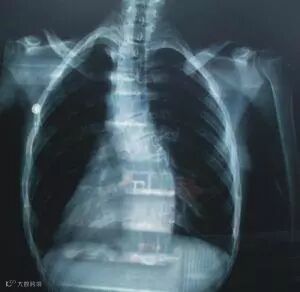

脊柱弯曲是指脊柱的一个或数个节段在冠状面上偏离身体中线向侧方弯曲,或在矢状面上后突或前突的增加或减少,形成一个带有弧度的脊柱畸形。通常还伴有脊柱的旋转,同时还有肋骨左右高低不等平、骨盆的旋转倾斜畸形和椎旁的韧带和肌肉的异常,它是一种症状或 X 线体征,可由多种疾病引起。脊柱侧弯通常发生于颈椎、胸椎或胸部与腰部之间的脊椎,也可以单独发生于腰背部。它会减小胸腔、腹腔和盆腔的容积量,还会降低身高。

脊柱弯曲是早已被世界公认为顽症的疾病,治疗难度大。如果严重的话会引起身体各大系统功能均受不同程度的影响,甚者会缩短寿命,危害巨大!

脊柱侧弯引起脊柱两侧受力不平衡,可引起腰背痛,并可在凹侧产生骨刺,压迫脊髓或神经,引起截瘫或椎管狭窄。脊柱侧弯造成了胸腹腔面积的减小,严重影响了患者的呼吸系统、消化系统、血液循环系统、内分泌系统等正常的生理功能,这一类病人中,成年以后,平均寿命普遍比正常人短,很多人死于心肺并发症。脊柱侧弯一半以上病人有腰腿疼,劳动能力下降,少数人甚至不能工作,严重时会导致下肢瘫痪,使病人完全丧失行动能力。脊柱侧弯给患者的正常工作、学习、生活、精神、婚姻、家庭等诸方面带来极大的困扰和不便。